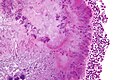

Microscopic

- Branching rods.

- Typically form pink/purple granules ("sulfur granule") that is surrounded by inflammatory cells (lymphocytes or neutrophils).